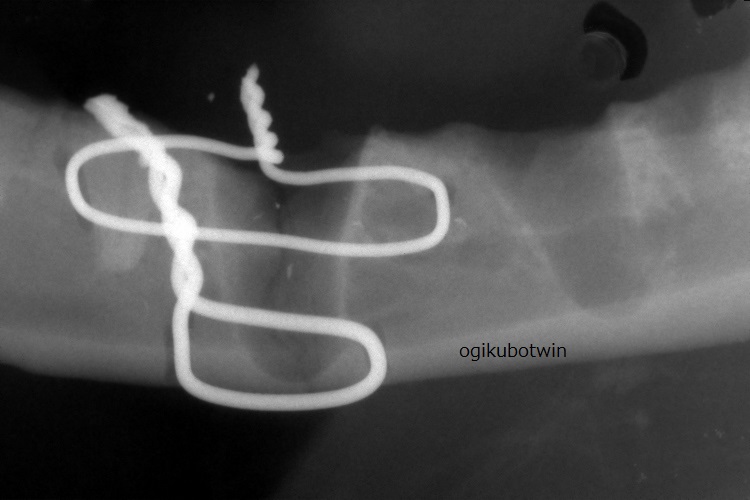

左下顎第一後臼歯(奥歯)と第四前臼歯の皮質骨にワイヤーを通して固定しました。

2週間後の検診の際にワイヤーが緩んでしまっていることが確認できたので、ワイヤーを3本に増やし、もう一度動揺しないよう、硬く締めなおしました。

骨折端は不安定でつながりにくいため顎間固定を行いました。

その後1週間の検診では顎の動揺は前回よりも少なくなり、再度ワイヤーを締め直して終了。

固定から2か月後、顎の動揺はほとんど見られない状況になり、固定器具を除去しました。